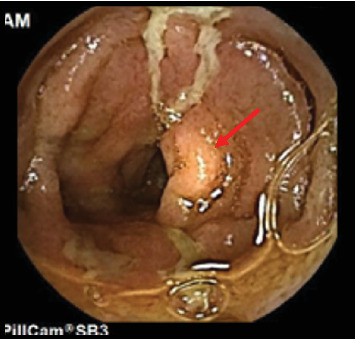

家族性地中海热(FMF)和克罗恩病(CD)是两种具有相似临床和生物学特征的慢性自身炎症性疾病。这两种疾病的特点都是慢性和复发性症状。在某些情况下,FMF可以与乳糜泻共存,这使得诊断和治疗具有挑战性。病例介绍:一名9岁的埃及儿童在5岁时根据临床症状和内窥镜组织病理学检查结果被诊断为乳糜泻。最初,患者对生物治疗(抗tnf α)反应良好,症状改善,炎症标志物和粪便钙保护蛋白水平下降。7岁时,患儿开始出现频繁发热并伴有胸膜炎性胸痛。多次胸部x光检查发现右侧胸腔积液。由于免疫抑制,患者被诊断为复发性急性细菌性肺炎,并接受了多个疗程的口服抗生素治疗。在最后一次报告中,在其中一次发作中,由于对抗生素缺乏反应,持续升高的炎症标志物(CRP, ESR)和无法解决的轻度右侧胸腔积液,因此进行了进一步的调查。根据患者的临床表现和胸部影像学,怀疑为FMF。详细的家族史显示,一位一级表亲有FMF阳性诊断。进行基因检测,发现两个杂合致病突变,支持FMF诊断。秋水仙碱治疗可防止进一步发作。患者继续接受胃肠道小组对CD的随访护理,并维持阿达木单抗。结论:对于表现出肺部症状且对乳糜泻治疗无反应的乳糜泻患儿,应考虑FMF。

Introduction: Familial Mediterranean fever (FMF) and Crohn's disease (CD) are chronic autoinflammatory disorders that share similar clinical and biological features. Both disorders are characterized by chronic and relapsing symptoms. In some cases, FMF can coexist with CD, which makes diagnosis and treatment challenging. Case Presentation: A 9-year-old Egyptian child was diagnosed with CD at the age of 5, based on clinical symptoms and endoscopic histopathologic findings. Initially, the patient responded well to biological therapy (anti-TNFα), showing improvements in symptoms along with declines in inflammatory markers and fecal calprotectin levels. At the age of 7, the child began experiencing frequent episodes of fever accompanied by pleuritic chest pain. Right-sided pleural effusion was identified on repeated chest X-rays. The patient was diagnosed with recurrent acute bacterial pneumonia due to immune suppression and was managed with multiple courses of oral antibiotics. During the last presentation, in one of these episodes, further investigation was pursued due to a lack of response to antibiotics, indicated by persistently elevated inflammatory markers (CRP, ESR) and nonresolving mild right-sided pleural effusion. FMF was suspected based on the patient's clinical presentation and chest imaging. A detailed family history revealed a positive FMF diagnosis in a first-degree cousin. Genetic testing was performed, which revealed two heterozygous pathogenic mutations that support the FMF diagnosis. Treatment with colchicine prevented further episodes. The patient continued to receive follow-up care from the GI team for CD and was maintained on adalimumab. Conclusions: FMF should be considered for children with CD who exhibit pulmonary symptoms that do not respond to CD treatment.